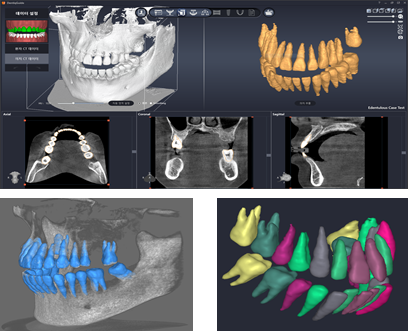

Our research center is being reborn as a global leading digital dentistry research Institute with its outstanding R&D talent on core technologies in the 3D Imaging field as well as dental solution field. 3DII continuously invests in R&D and conducts activities to secure and apply new technologies for AI, Big Data, Cloud, and Digital Transformation.